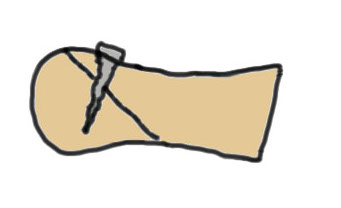

Modified Weil osteotomy

Modification

Take wedge of bone out dorsal

Dorsiflex metatarsal head

Results

Kim et al Clin Orthop Surg 2012

- Weil osteotomy for 20 cases Freibergs

- 95% good or excellent